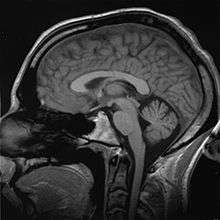

Brain

"It is well established that men have a larger cerebrum than women by about 8–10% (Filipek et al., 1994; Nopoulos et al., 2000; Passe et al., 1997a,b; Rabinowicz et al., 1999; Witelson et al., 1995)."[91][92] However, what is functionally relevant are differences in composition and "wiring". Richard J. Haier and colleagues at the universities of New Mexico and California (Irvine) found, using brain mapping, that men have more grey matter related to general intelligence than women, and women have more white matter related to intelligence than men – the ratio between grey and white matter is 4% higher for men than women.[91]

Grey matter is used for information processing, while white matter consists of the connections between processing centers. Other differences are measurable but less pronounced.[93] Most of these differences are produced by hormonal activity, ultimately derived from the Y chromosome and sexual differentiation. However, differences that arise directly from gene activity have also been observed.

It has also been demonstrated that brain processing responds to the external environment. Learning, both of ideas and behaviors, appears to be coded in brain processes. It also appears that in several simplified cases this coding operates differently, but in some ways equivalently, in the brains of men and women.[95] For example, both men and women learn and use language; however, bio-chemically, they appear to process it differently. Differences in female and male use of language are likely reflections both of biological preferences and aptitudes, and of learned patterns.